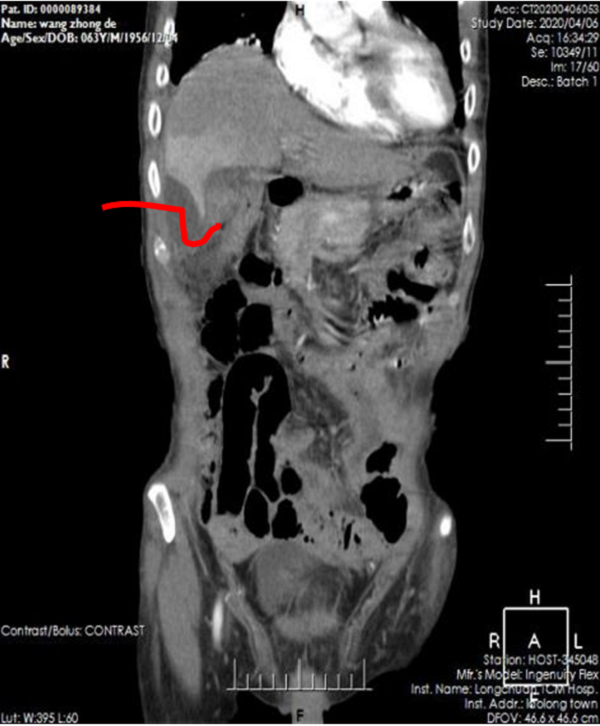

4月9号下午四点,在完善各种医疗文书工作以及各项术前准备后,李嘉医生在B超引导下对患者行腹腔多发脓肿精准穿刺引流。该院B超室团队细致、耐心地引导穿刺导丝以及穿刺针成功地在不到1.3cm的间隙中,避开了肠道以及右肝外叶,将5mm的引流导管头部精准引导入肝下脓肿处。同时引流导管侧孔无偏差地对准于肝肾隐窝脓肿处,精确地引流出两处脓肿,完美地达到术前既定方针。

引流管走向示意图,避开右肝下缘、肠道